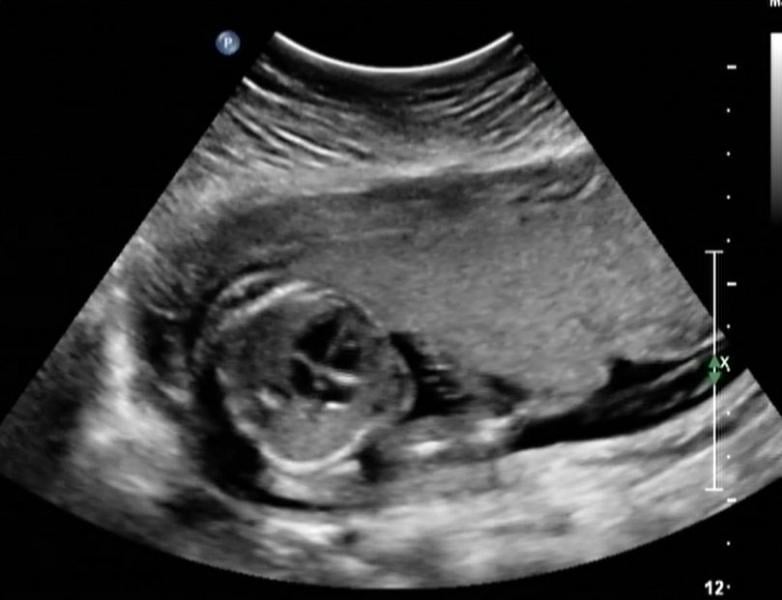

Below is a collection of prenatal ultrasound pictures from the Imaging Technology News (ITN) archive. Use the arrows to click through the image gallery. It includes transvaginal ultrasound images and fetal echocardiogram images. Fetal imaging is referred to by many names, including pregnancy sonograms, pregnancy ultrasound, endovaginal ultrasound, obstetric ultrasound, OB ultrasound, baby ultrasound, prenatal ultrasound. Fetal heart ultrasound is also called baby echo or prenatal echo.